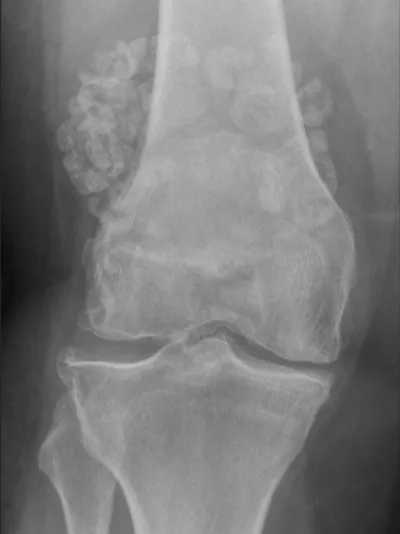

Osteoarthritis Radiology Images

Browse 3 medical images tagged with osteoarthritis. This collection includes various imaging modalities for medical education and reference.

- This collection contains 3 radiology images related to osteoarthritis, including various imaging modalities such as X-rays, MRIs, CT scans, and ultrasound images commonly used in medical diagnosis and education.